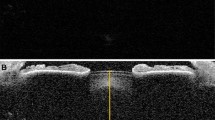

All subjects were seated in front of the AC biometer and focused on a defined internal target with the study eye. Corneal thickness, ACD, and LT (Fig. 1) were measured using best-distance correction, representing the unaccommodated eye. Afterwards, AC biometer measurements were performed under maximal accommodation. The unmeasured eye was occluded, and the subject had to focus on the fixation target, which was blurred by negative spherical glasses. Accommodation of up to −5 D was presented within the AC biometer. If a patient was able to accommodate more than 5 D, additional minus glasses in a trial frame were used. The examined eye had to accommodate in order to see the cross clearly. Minus dioptres were added until the subject saw the cross blurred. Measurements were taken at that dioptre step, where the subject was still able to visualise the fixation target clearly. A set of at least ten successful measurements was taken while the subject was continuously motivated to accommodate and to focus on the cross. For further analyses, the median of the consecutive measurements was used.

Corneal thickness was defined as the distance from the anterior corneal surface (ACS) to the posterior corneal surface (PCS), the ACD as the distance from the PCS to the anterior lens surface (ALS), and the LT as the distance from the ALS to the posterior lens surface (PLS).

The anterior eye segment (AS) was defined as the distance between the PCS and PLS. The anterior cortex (AC) was defined as the distance from the ALS to the anterior nucleus surface (ANS). The posterior cortex (PC) was defined as the distance between the posterior nucleus surface (PNS) and the PLS, and the nucleus thickness as the distance between the ANS and the PNS.

For detecting nucleus thickness (NT), the ANS and the PNS were evaluated. A graphically averaged A‑scan of all measurements in each eye under the same conditions was used. The scan was enlarged by the software, and a significant signal peak near the ALS was detected by the software. For this purpose, the PLS cursor was set to this signal peak. Then, for evaluating PNS, the same procedure was set to the posterior cortex (PC) interface peak. Additionally, all data were analysed manually to verify the findings of the software.